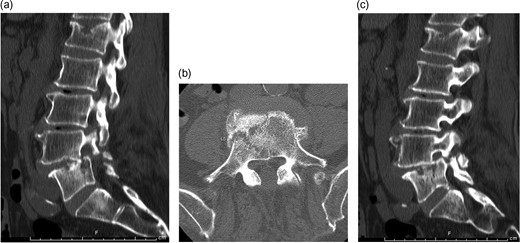

Median, parasagittal and axial images from a lumbar CT scan obtained following review of the patient's lumbar radiographs. (a) Sagittal CT demonstrating vertebral body split. (b) Axial CT demonstrating vertebral body fracture at L5. (c) Sagittal CT demonstrating pars fractures at L4.